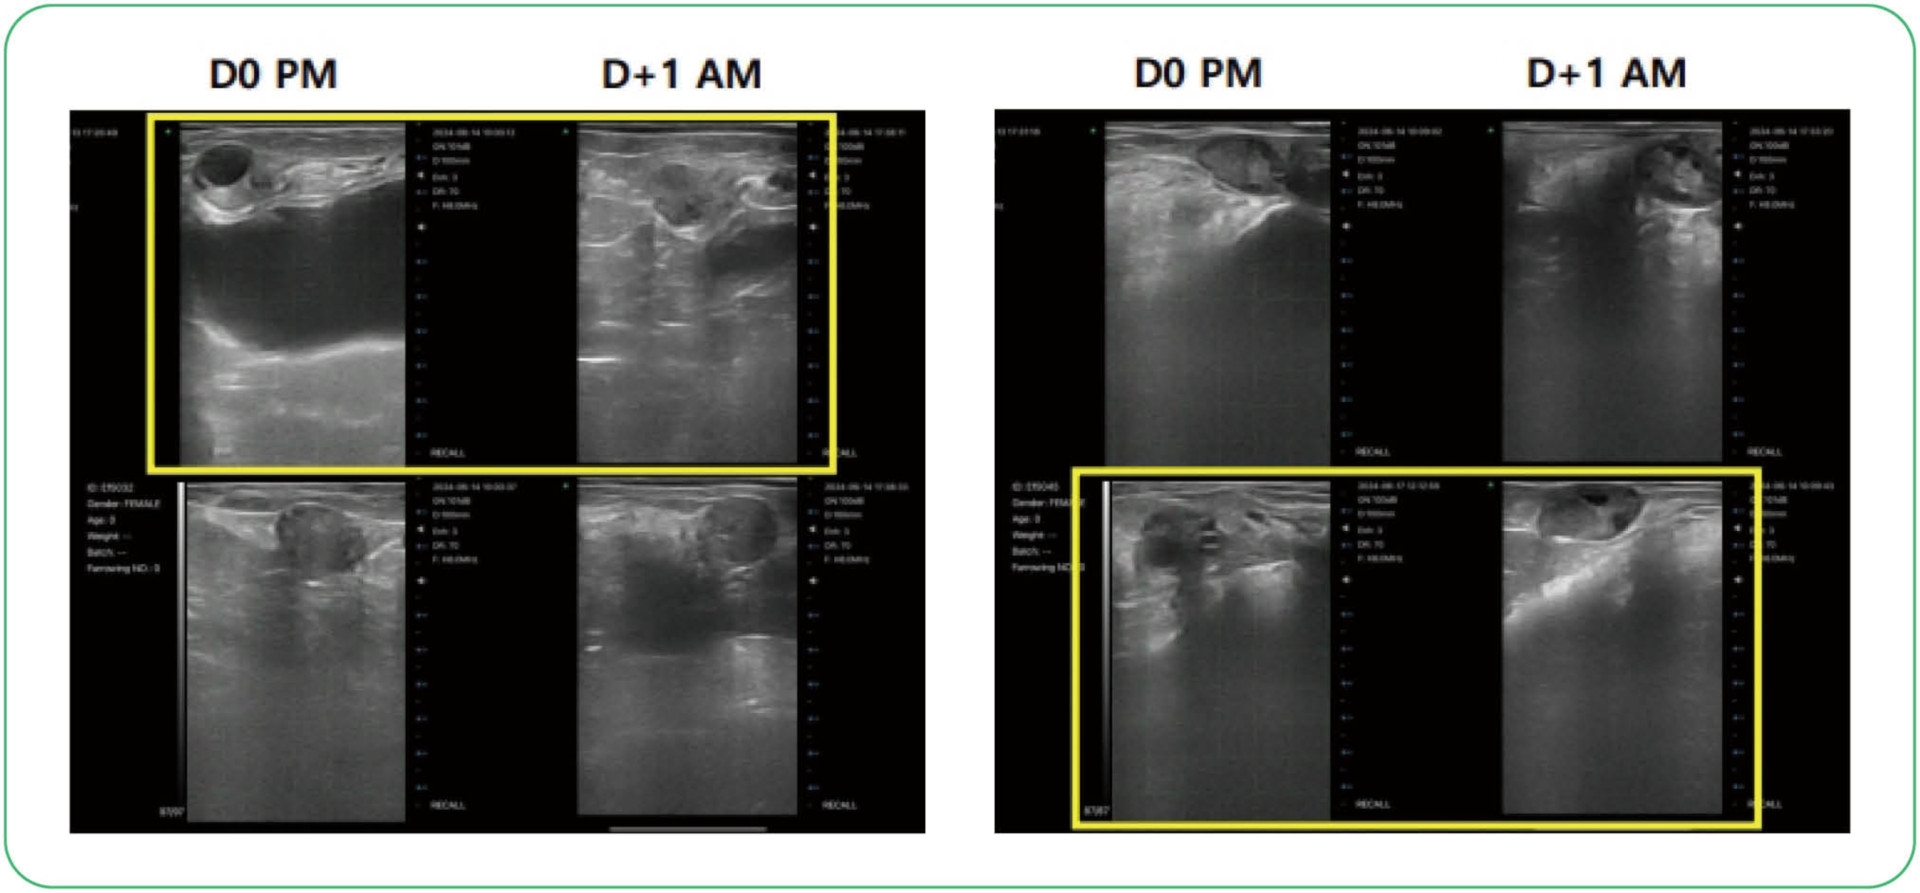

▲ 배란시기 확인을 위한 난소 초음파 사진